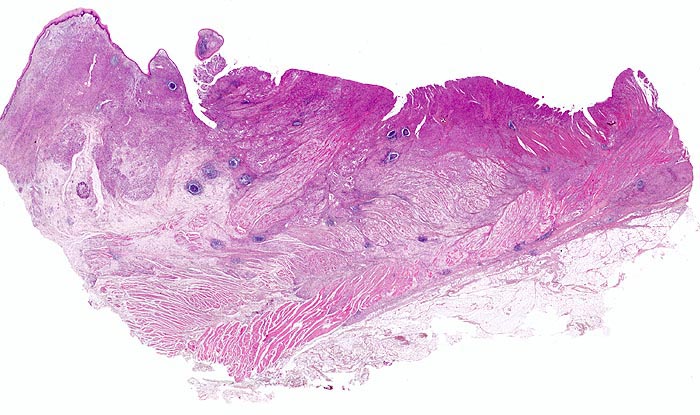

• Gewebsfragment aus gastroösophagealem Übergang.

• Das unscharf begrenzte Karzinom breitet sich diffus in der gesamten Magenwand und in der Ösophaguswand aus bis in des periösophageale und subseröse Fettgewebe.

• Ösophagus mit intaktem plattenepithelialem Schleimhautüberzug.

• Ein Grossteil des Tumorinfiltrats besteht aus einzeln oder in kleinen Gruppen liegenden Zellen mit intrazytoplasmatischen Schleimvakuolen, die teilweise den Kern verdrängen (Siegelringzellen): diffuser Typ des Magenkarzinoms nach Lauren.